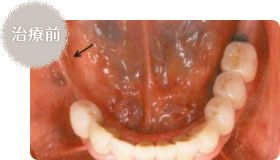

- 右下の奥歯を失くしてしまいました

- 右下の部分入れ歯を入れた状態

部分入れ歯(部分床義歯)は、総義歯と違い、歯にかける鉤(クラスプ)がある、失った歯の本数や位置によって床の形や大きさが違います。入れた当初は違和感があったり、喋り難かったりしますが、多くの患者さんが次第に慣れてきます。

多数の歯が失われている場合

※欠損歯が少数で両隣在歯が健康な場合には、ブリッジによる治療が可能